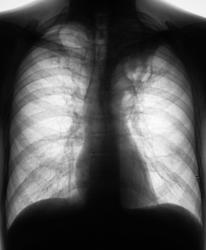

Пациент в 2007, 2008 гг. проходил профилактическую флюорографию - иллюстрации ниже. При прохождении флюорографиив 2009 г. "картинка" резко отличается от предыдущих.

1.Флюорограммы за 2007, 2008 гг. представлены, оценены, как норма.

2. Мужчина, 48 лет.

3. Жалобы на общую слабость. Больше жалоб никаких. В последнее время - кашель, мокрота беловатого цвета, имеются прожилки крови. Внешне - пациент недостаточного питания, анемичен, живет в семье.